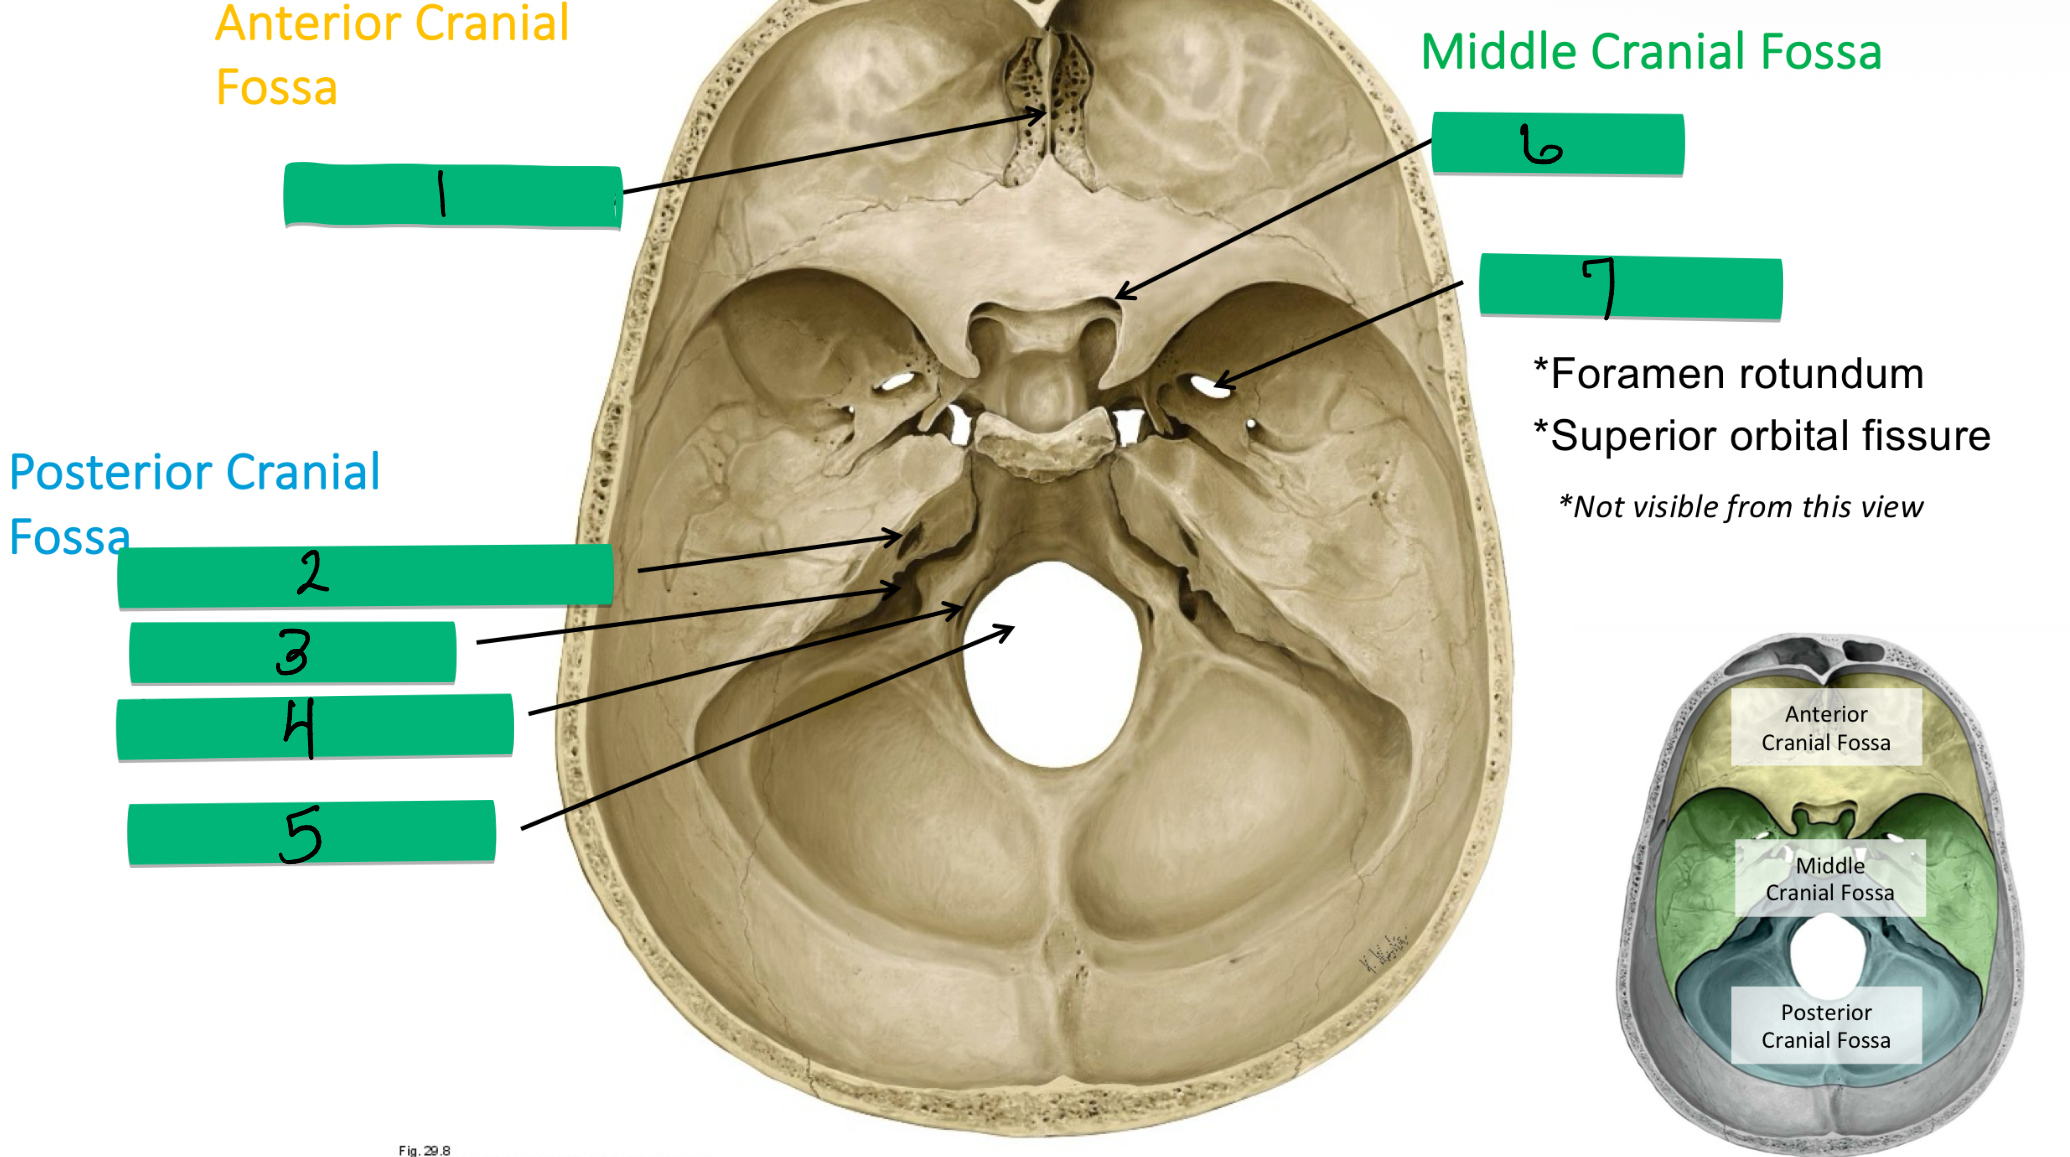

Name 1 and nerve

Cribriform plate: CN I

Name 2 and nerve

Internal acoustic meatus: CN VII and VIII

Name 3 and nerve

Jugular foramen: CN IX, X, XI, Internal jugular vein

Name 4 and nerve

Hypoglossal Canal: CN XII

Name 5 and nerve

Foramen magnum: CN XI

Name 6 and nerve

Optic canal: CN II

Name 7 and nerve

Foramen ovale: CN V3

1

2

Superior Orbital Fissure: CN III, IV, V1, VI

3

Foramen Rotundum: V2